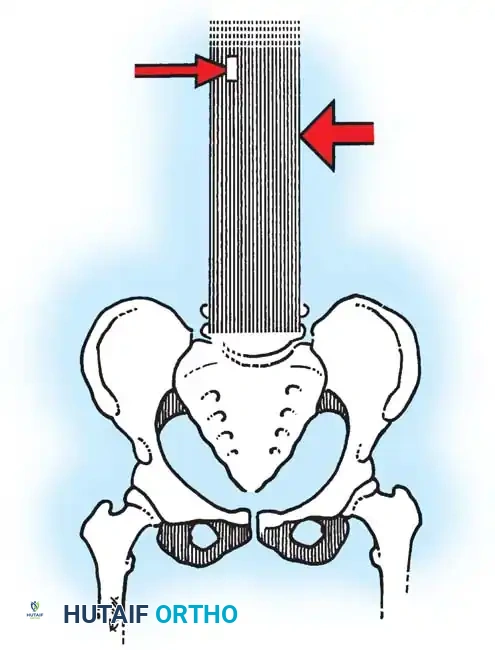

Fig. 38-22: Patient positioning on a Jackson table with hips in extension to maintain physiological lumbar lordosis.

Positioning on the Jackson Table

- Prone Positioning: The patient is carefully rolled prone onto an open-frame Jackson table (e.g., Mizuho OSI, Union City, Calif). The open frame is paramount as it allows the abdomen to hang free.

- Hemodynamic Optimization: Eliminating intra-abdominal pressure prevents compression of the inferior vena cava. This directly reduces venous engorgement within Batson’s epidural venous plexus, drastically minimizing intraoperative blood loss during exposure and pedicle cannulation.

Surgical Warning: When a patient is positioned prone with the hips flexed, physiological lumbar lordosis is artificially obliterated. If the planned fusion extends into the lower lumbar spine (L3, L4, or L5), it is imperative to elevate the knees and thighs so the hip joints are fully extended. This maneuver restores and locks in normal lumbar lordosis, which is critical for preventing postoperative flatback syndrome and adjacent segment disease.